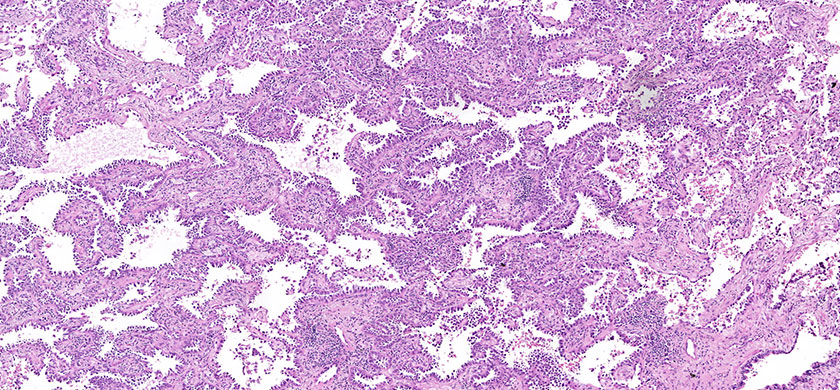

Besides, BioPartners offers slide scanning services to medical professionals and organizations at very affordable prices. What you need to do is to send us your glass slides with the completed order form and you will get them back along with the high-resolution and extra-quality virtual slides. Digital slides are either delivered on a DVD (in case of 1-2 glass slides) or an external hard drive. The slide viewing software will be provided as well. Scan type: illumination – bright field, objective magnification – 20x. Approximate size of the digital slide will be between 700MB and 2.5Gb. On your request, your FFPE (formalin fixed, paraffin embedded) or TMA tissue sample can be microtomed and H&E stained.